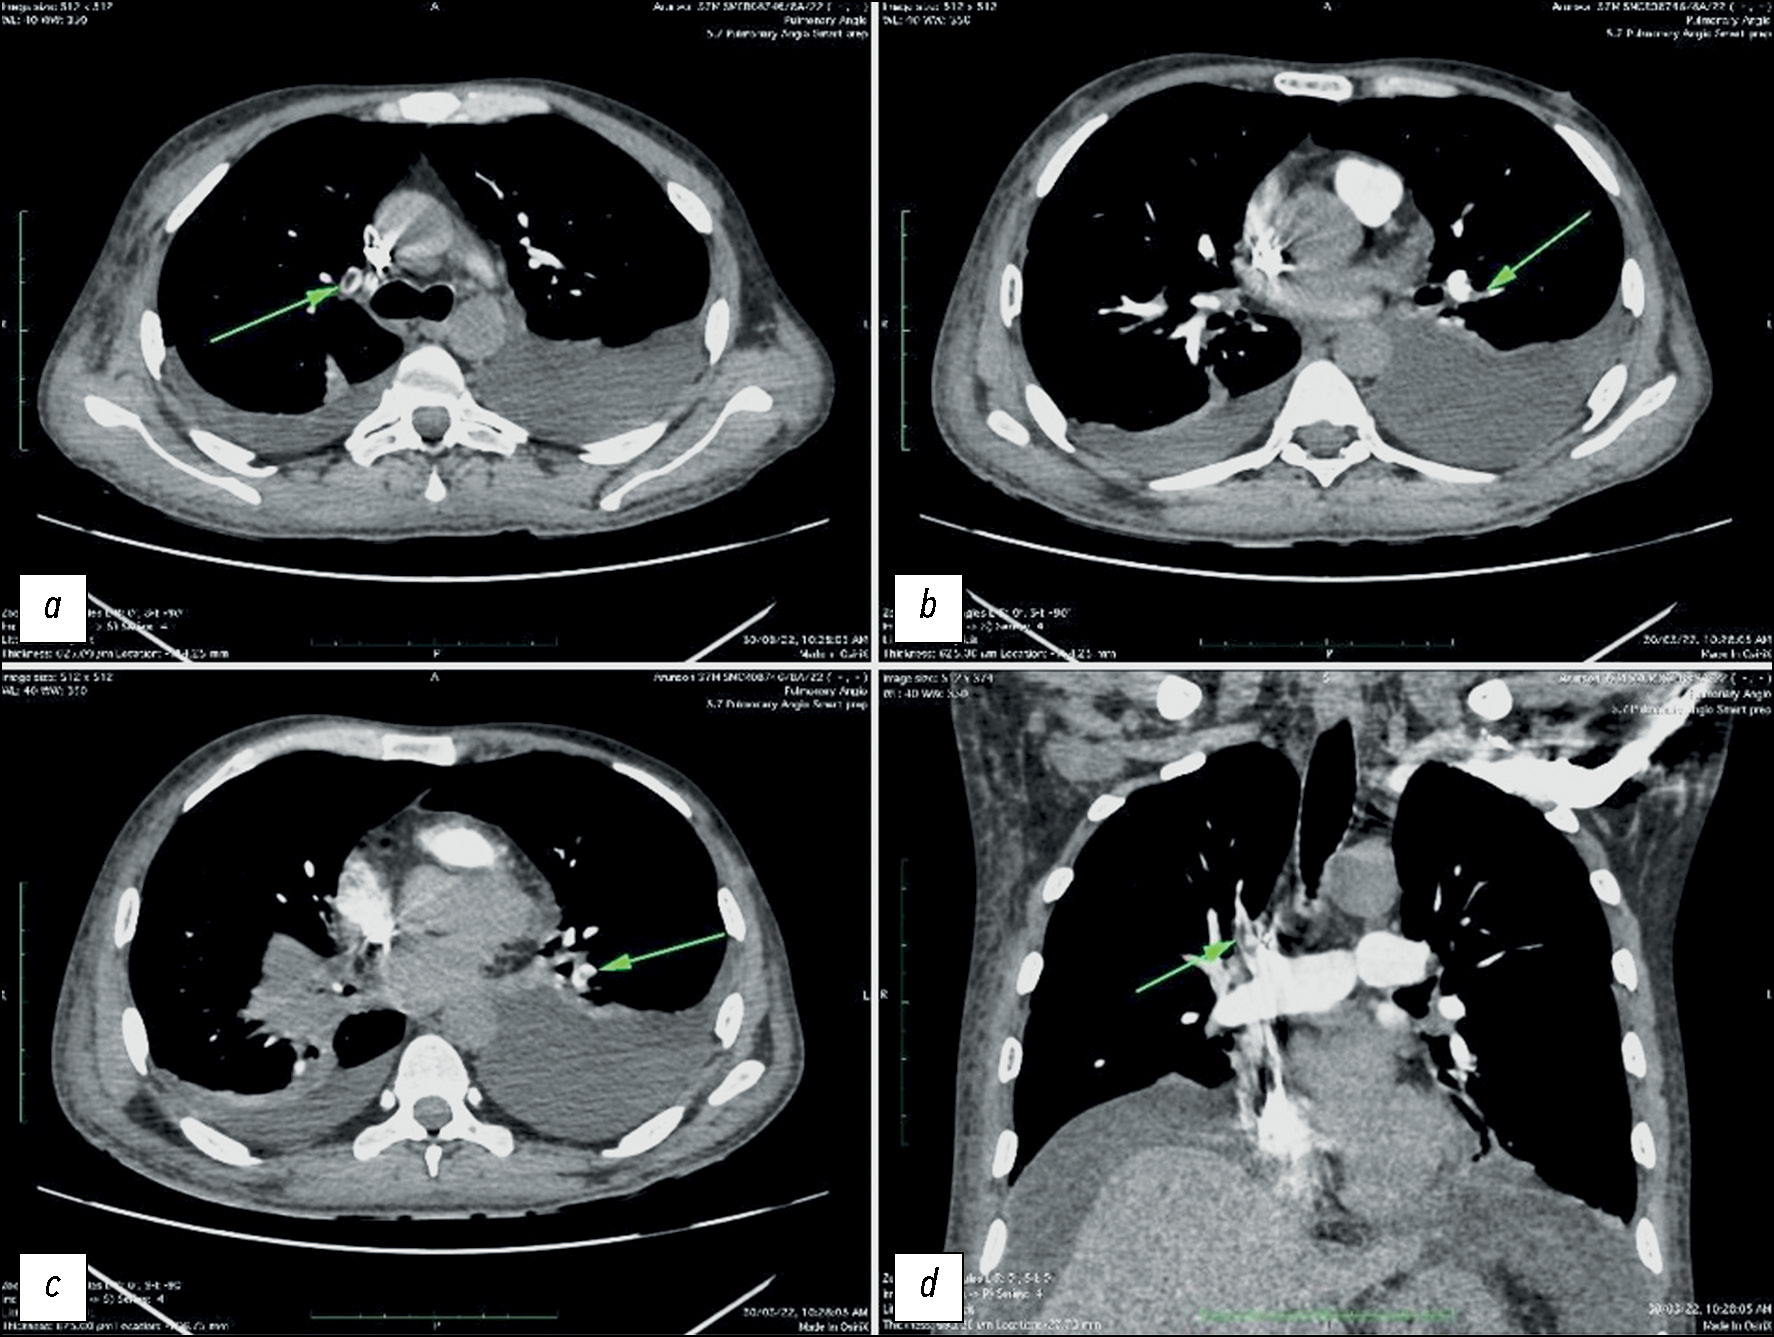

通过计算机断层扫描血管造影发现年轻肺动脉高压患者的肺动脉假性动脉瘤

摘要

假性动脉瘤和肺动脉瘤是一种罕见的疾病,但与之相关的并发症强调了识别它们的重要性。本文介绍了一名15岁患者的临床病例,该患者因咯血而入院。经诊断,发现左肺动脉瘤。随后的计算机断层扫描血管造影和肺动脉介入治疗结果证实存在肺动脉瘤,这表明咯血是由于动脉瘤破裂造成的。肺动脉介入证实了确诊。肺动脉瘤的早期发现和治疗至关重要,尤其是对年轻患者,因为及时干预可以预防严重并发症,改善疾病预后。提高对这些血管疾病的认识,并通过相应的诊断措施和干预措施对其进行及时处理,可以帮助医疗服务者有效降低与肺动脉瘤相关的潜在风险,从而提高预后准确性和医疗服务质量。